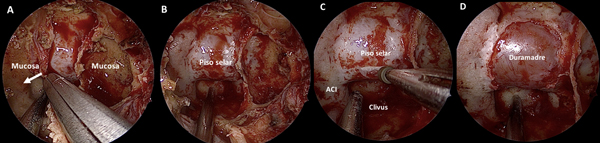

El próximo paso es identificar el ostium esfenoidal del lado derecho. Si el mismo no es visible, la maniobra más recomendada para identificarlo es utilizar un disector de Cottle para lateralizar el cornete superior en la unión de su tercio medio y posterior. Si aun así no logra identificarse, se procede palpando sin presionar demasiado en esta región hasta identificar una zona débil fenestrando delicadamente la mucosa. Se realiza finalmente un movimiento rotacional con el disector para ampliarlo (Figura 2 A-B).

La zona más baja del ostium coindice con el “punto de Cappabianca”, 12 mm por arriba del techo de la coana.10 (Figura 3 A-D) A partir de este punto comenzamos el tallado de un “mini-rescue flap” septal del lado derecho. Utilizamos una punta de colorado de 45 grados a tales efectos. Se trata de una modificación del rescue flap que utiliza el equipo de Ohio11; el corte anterior se efectúa buscando la proyección de la unión osteo-cartilaginosa septal (Figura 2 C-E).

Una vez expuesta esta región, se realiza con un disector presión sobre la misma, buscando la desinserción osteo-cartilaginosa (Figura 2F).

Acto seguido, se realiza una pequeña ventana en la parte posterior del septum a expensas del segmento óseo con una pinza punch. Es una mínima ventana que tiene como único objetivo permitir el acceso de instrumental a través de la otra fosa nasal (Figura 2G). Se utiliza de este modo 1 narina (la derecha) y ½ (izquierda). Se procederá entonces a identificar el ostium esfenoidal contralateral utilizando la técnica antes descripta. Se objetivan así, ambos ostium y la quilla esfenoidal (Figura 2H).

Figura 2. Fase naso-esfenoidal. A-B: identificación mediante palpación y apertura con maniobra rotacional del ostium esfenoidal. C-D: tallado del mini-rescue flap. E-F: septum denudado y desinserción osteo-cartilaginosa. G: exposición de mucosa contralateral luego de septectomía posterior; en línea de puntos se delimita el sitio de corte. H: rostro de oso hormiguero luego de exponer el rostrum esfenoidal.

Se procede a la apertura del rostrum esfenoidal, la cual debe ser siempre amplia. Muchas veces es esto lo que proporciona un adecuado surgical freedom y no la amputación de estructuras nasales. Luego, se resecan todos los septos intrasinusales y se exentera la mucosa a fines de exponer con claridad todos los reparos anatómicos: la prominencia del piso de la silla turca al centro, la silueta de ambas arterias carótidas internas a los lados, el planum esfeno-etmoidal arriba y el clivus abajo (Figura 4 A-B).

Figura 3. Preparado cadavérico que muestra reparos a la hora de tallar el mini-rescue flap. A: receso esfeno-etmoidal. B: ídem a A con nomenclatura. C: zoom para evidenciar arteria esfenopalatina en receso esfeno-etmoidal. D: correlación entre el punto de Cappabianca (circulo celeste con borde blanco) y el borde inferior del ostium esfenoidal.

Figura 4. Tiempo intrasinusal. A-D: exposición de la duramadre selar.

En la fase selar la pared posterior del seno esfenoidal (i.e la prominencia selar) es fresada con punta diamantada a fines de disminuir su espesor (Figura 4C). Luego, se realiza una apertura “a medida” utilizando una pinza de Kerrison N°1. El plano dural queda expuesto hasta evidenciarse los “cuatro azules” o la “corona azul” (i.e. el limite más medial de ambos senos cavernosos y el límite de ambos senos intercavernosos)14 (Figura 4D).